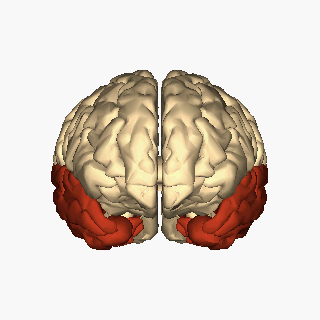

Scientists can get some insight into the neural underpinnings of déjà vu by comparing the brains of people who have experienced déjà vu and those who never have. Using MRI (magnetic resonance imaging, a technique that lets researchers non-invasively look at the structure and activity levels of the brain), scientists found that people who experience déjà vu have structural differences in the composition of the brain. The main brain region associated with déjà vu is the medial temporal lobe (Figure 1). This brain area includes the hippocampus and parahippocampal gyrus, which are involved in memory formation and storage.

Déjà vu is associated with decreased gray matter – a type of brain tissue that contains cell bodies – in regions such as the basal ganglia, thalamus, insular cortex, and mesiotemporal areas including the hippocampus4.These structural differences in areas associated with memory formation, emotion, and sensory processing may explain why some people experience déjà vu while others do not.

The functional connectivity, or ways that different regions of the brain communicate with one another, is also altered in the brains of people who frequently experience déjà vu. These people have altered strength of connectivity between regions of the parahippocampal gyrus (an area associated with memory and familiarity) and the dorsolateral pre-frontal cortex (dfPFC), compared to people who rarely or never experience déjà vu5. One hallmark of déjà vu is an awareness that the familiarity you feel isn’t correct. The dlPFC is involved in monitoring errors, so it is likely involved in alerting that brain when its sense of familiarity isn’t quite right.